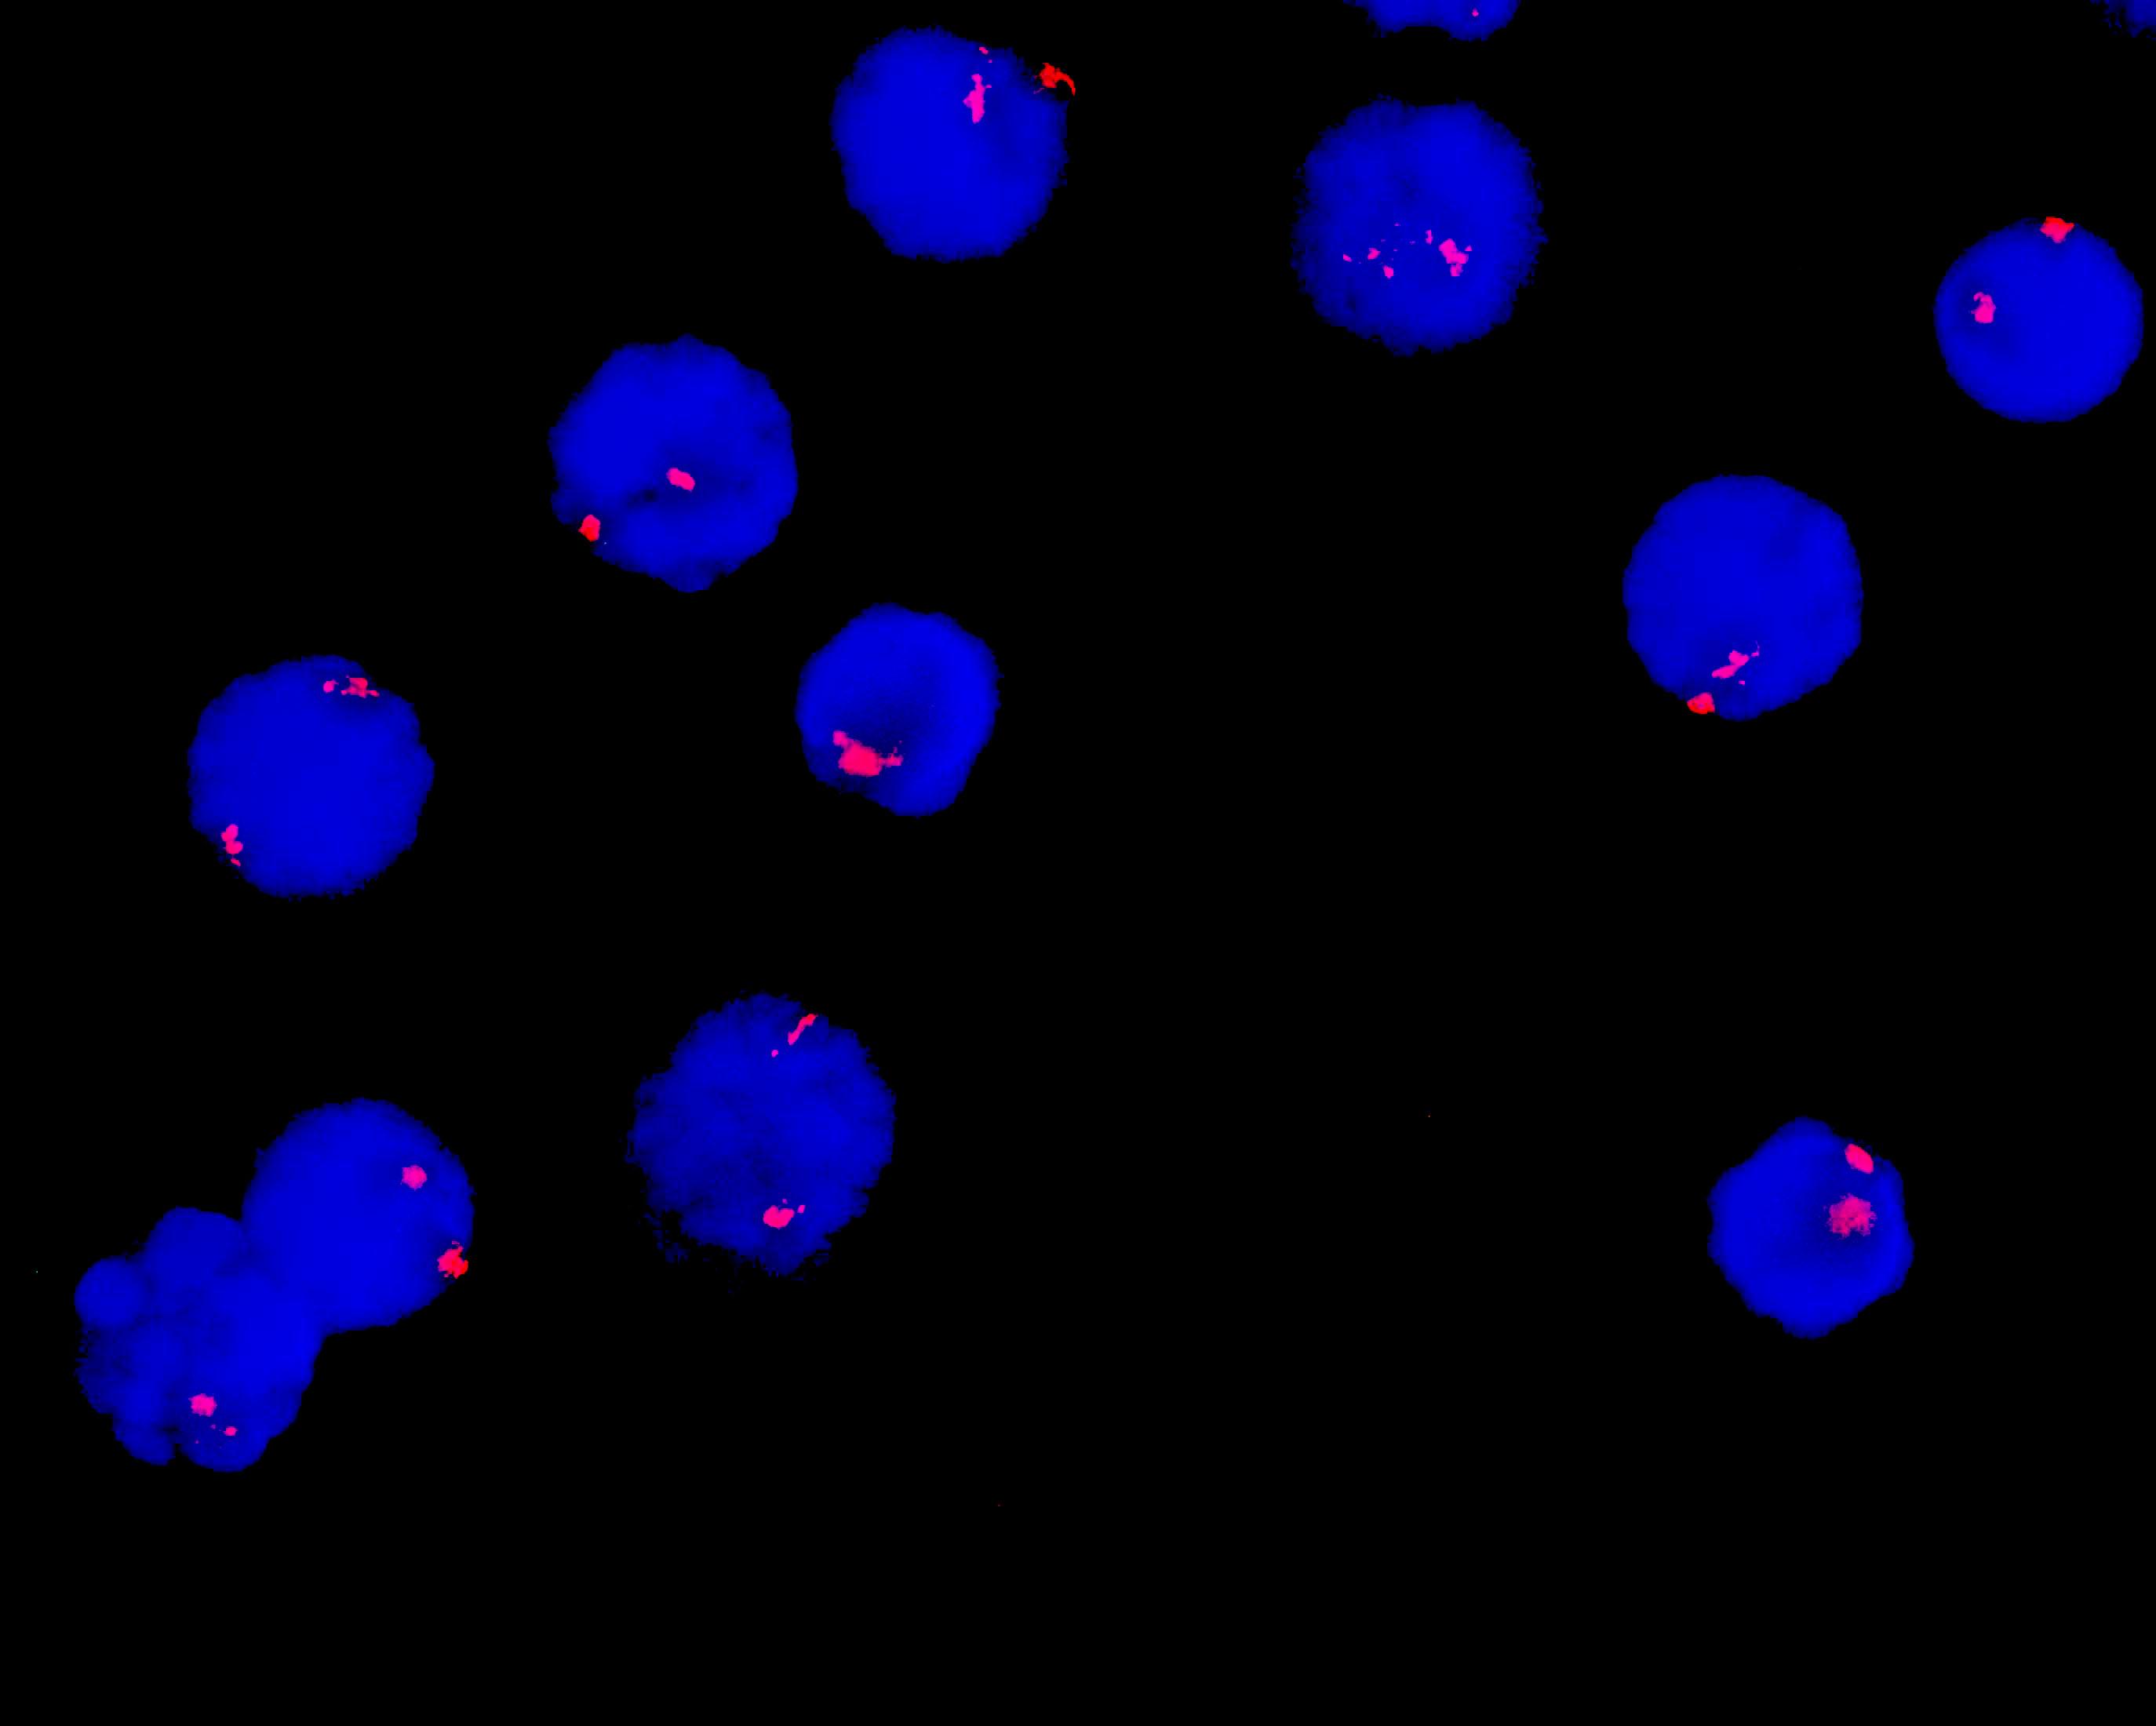

Chromosome 12 centromere probe reagent

Chromosome 12 centromere probe reagent

CEP12 orange probe

12 chromosome centromere (CEP12) labeled as orange.